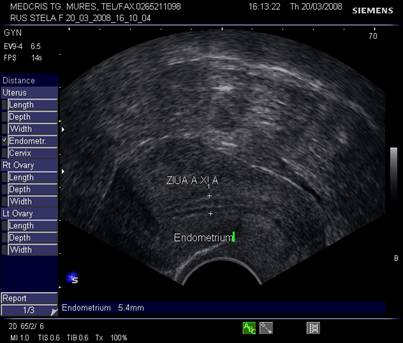

Dupa Deichert si Michaels[4] se disting 4 structuri endometriale diferite, la ecografia transvaginala:

Tipul proliferativ - hipoecogen, apare cu aceeasi ecogenitate ca si miometrul. Apare dupa menstruatie si in faza medie proliferativa. Are un ecou central liniar .

Tipul periovulator - are limita ecogenica distincta cu miometrul adiacent si un ecou liniar central (imagine de inel cu linie pe mijloc).

Grosimea endometrului este de circa 1-2 mm la inceput de faza proliferativa, de cca 5 mm in ziua 10 -11, cu 1 zi preovulator cca 10 - 12 mm,apoi stagneaza, toate acestea la un ciclu menstrual de 28 zile.[2,6]